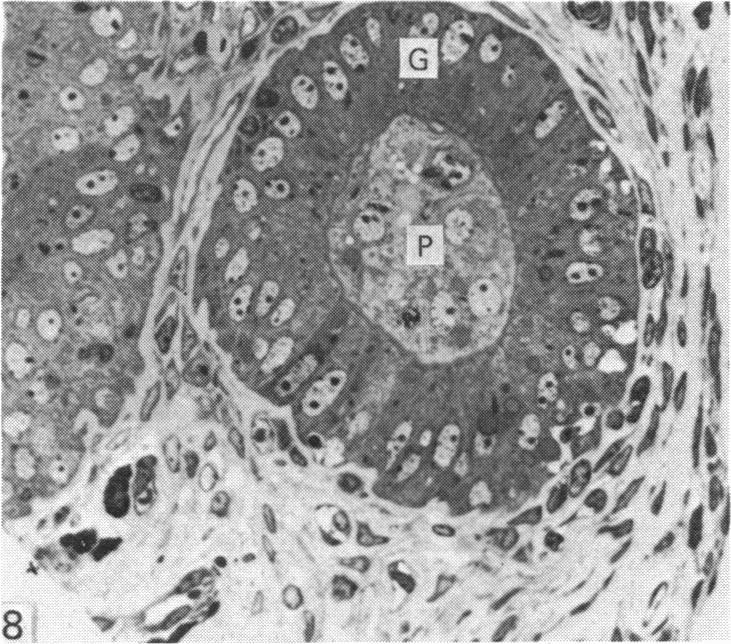

Structure of trophoblast papillae on the sheep conceptus at implantation.

A study of 13-18 days old sheep conceptuses has consistently demonstrated the presence of multicellular protrusions (papillae) from the trophectoderm surface. These papillae were shown to be restricted to the embryonic region of conceptuses flushed out of the uterus. After perfusion fixation of the uterus on day 16 of pregnancy, the papillae can be observed penetrating well down into the lumina of the uterine glands. The papillae have not been observed at or after day 20. It is suggested that the papillae may play an important but transient role in anchoring the embryonic region of the conceptus against the uterine epithelium to allow the initiation of the cellular changes characteristic of implantation.